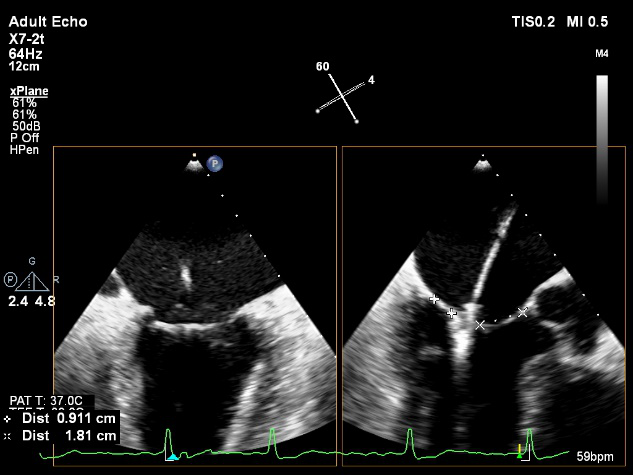

术中超声

确定房间隔穿刺点:靠后

2D视图下测量大鞘长度2cm

3D视图打开夹子

X-plane:下第夹子尝试捕获2区

X-plane:测量前叶长25mm,后叶长14.2mm

X-plane:计算前叶捕获长度8mm,后叶捕获长度7mm

3D视图下观察二尖瓣双孔形态

3D-color:残余少量返流